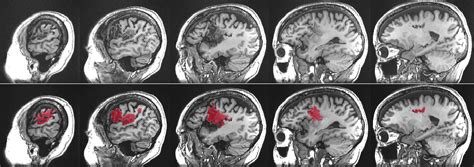

So, what is aphasia ? At its core, aphasia is a language disorder resulting from damage to the parts of the brain that control language. It’s not a problem with intelligence; people with aphasia are just as smart as they were before. Instead, their ability to process and use language has been impacted. Think of your brain as a super-complex computer. Language is one of its most sophisticated programs. When that program gets corrupted or parts of the hardware are damaged, it can lead to difficulties in understanding spoken or written language, or in expressing oneself through speaking, writing, or even gestures. It’s important to remember that aphasia can manifest in many different ways, depending on the location and extent of the brain damage. Some people might struggle to find the right words, others might have trouble understanding what others are saying, and some might experience a combination of these difficulties. It’s a spectrum, guys, and each person’s experience with aphasia is unique. The key takeaway here is that aphasia affects communication, not cognition. Someone with aphasia can still think, reason, and feel, but they might have a hard time expressing those thoughts or understanding yours clearly. We’ll delve deeper into the types of aphasia and their specific challenges as we go on, but for now, grasping this fundamental distinction is key to understanding the condition.

Let’s talk about causes of aphasia . Understanding what triggers this language disorder is super important for prevention and treatment strategies. The primary cause of aphasia is damage to the language-dominant areas of the brain. For most people, the left hemisphere of the brain is responsible for language functions. When these areas are injured, aphasia can result. The most common culprit, as we’ve touched upon, is a stroke . Strokes occur when blood supply to a part of the brain is interrupted, either by a blockage (ischemic stroke) or by bleeding (hemorrhagic stroke). This lack of blood flow deprives brain cells of oxygen, causing them to die. Depending on which part of the brain is affected, language abilities can be severely impacted. Another significant cause is Traumatic Brain Injury (TBI) . TBIs can happen from blows to the head, falls, or accidents. The widespread nature of the damage in a TBI can affect various brain functions, including language. Brain tumors can also lead to aphasia . Whether the tumor is malignant or benign, its growth can press on or invade brain tissue, disrupting normal function, including language processing. Brain infections , such as encephalitis (inflammation of the brain), can also cause damage to language areas. Lastly, neurodegenerative diseases are a cause, particularly Primary Progressive Aphasia (PPA). PPA is a group of brain disorders caused by specific types of dementia that target the brain’s language networks. Unlike other causes where aphasia might appear suddenly, PPA is typically a gradual decline. Each of these causes of aphasia presents unique challenges in terms of diagnosis, treatment, and prognosis. Knowing the cause helps medical professionals tailor the approach to managing aphasia , aiming to restore as much language function as possible and improve the quality of life for those affected. It’s a complex puzzle, and identifying the root cause is a critical piece.

Now, let’s get into the nitty-gritty: the types of aphasia . Because aphasia is caused by damage to different parts of the brain, it doesn’t just show up as one single problem. Instead, it’s classified into various types, each with its own set of characteristics. This classification helps speech-language pathologists (SLPs) understand the specific challenges a person is facing and develop targeted therapy. The two main categories are often fluent aphasia and non-fluent aphasia , with further subtypes within each.

Fluent Aphasia

In fluent aphasia , individuals can speak easily and smoothly, often at a normal rate. However, what they say may not make sense. They might use made-up words (neologisms) or substitute incorrect words (paraphasias). Comprehension is often impaired. The most well-known type of fluent aphasia is Wernicke’s aphasia . People with Wernicke’s aphasia can speak fluently but often produce nonsensical speech, sometimes referred to as a